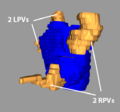

- Carma 4RPV.png 600 × 600; 193 KB

- Carma 4rpvs.png 600 × 600; 165 KB

- Carma Norm LPVs.png 651 × 631; 138 KB

- Carma Norm RPVs.png 593 × 551; 115 KB